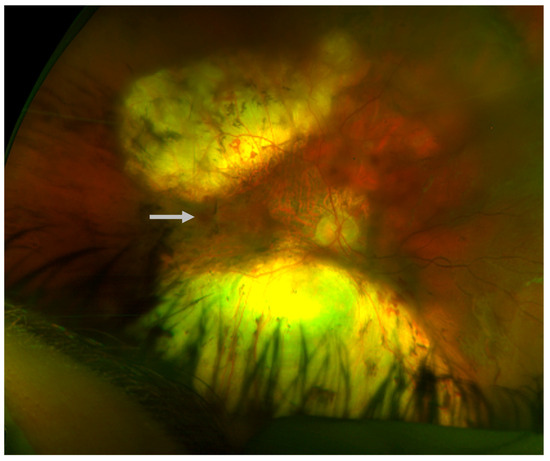

Figure 2.

Chorioretinal atrophy of the left eye; macular view (left) and nasal retina (right), age 10.

An 8-year-old male presented to the pediatric ophthalmology clinic for evaluation of possible strabismus and poor vision. Past medical history was significant for microcephaly- and lymphedema-related developmental delays requiring special education and speech therapy, as well as a history of seizures (in remission without antiepileptic drugs for at least one year). The patient had been clinically diagnosed with microcephaly–lymphedema–chorioretinal dysplasia syndrome (MLCRD) prior to presentation. His height and weight were in the fifth percentile for his age. Family ocular history was positive only for strabismus, and there was a maternal family history of hereditary lymphedema. Upon initial examination, visual acuity was 20/400 eccentrically in the right eye with a correction of −0.50 +1.00 × 180 and 20/60 in the left eye with a correction of −0.50. Visual fields were full to confrontation, and extraocular movements were normal. The anterior segment examination was within normal limits. A dilated fundus exam demonstrated areas of retinal pigment epithelium deposits and chorioretinal atrophy (CRA) bilaterally (Figure 1 and Figure 2).